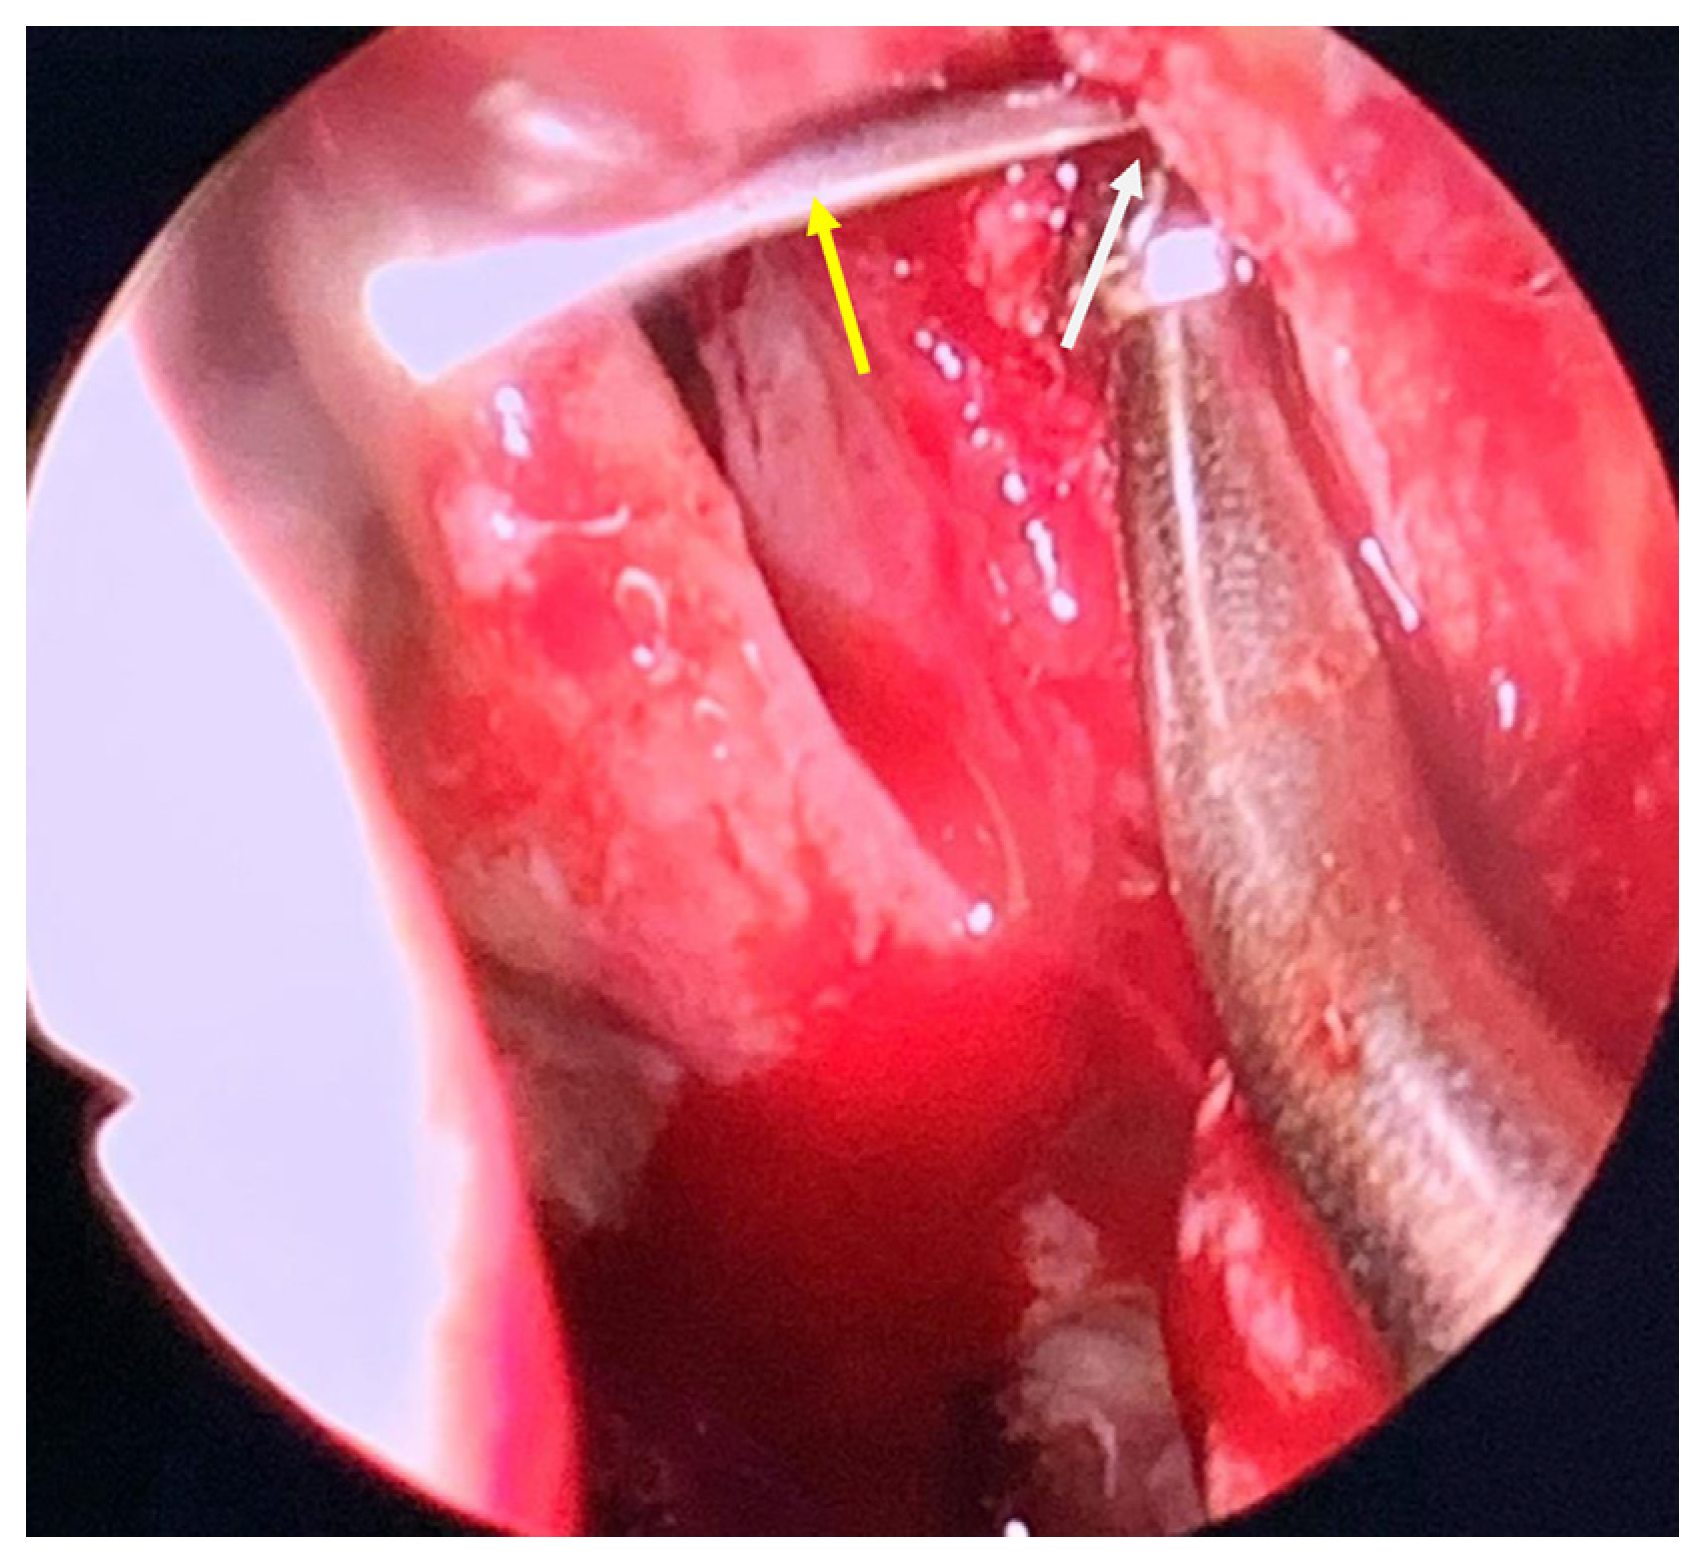

2. Case Report